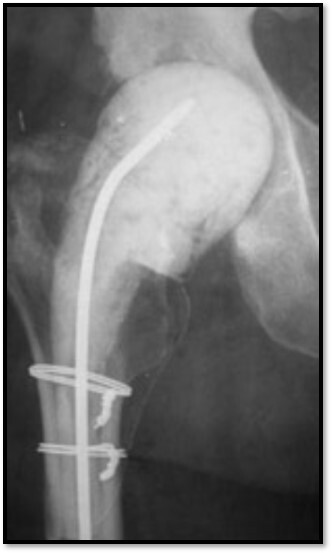

What is this showing here?

Infected arthroplasty

Antibiotic leads